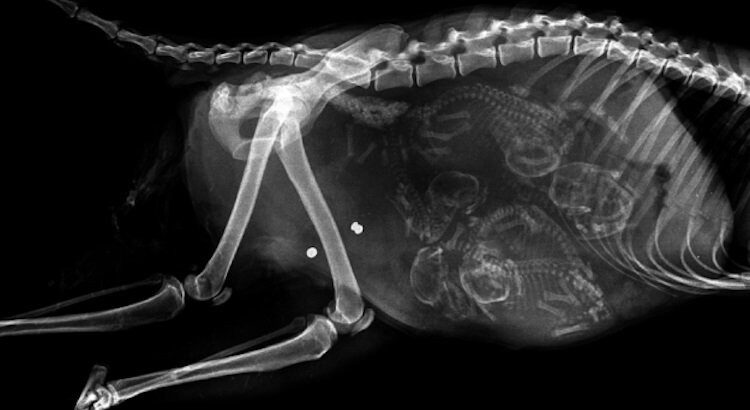

Le saviez-vous ? Le chat est une sous-espèce issue de la domestication du chat sauvage, qui vient lui-même de la famille des félidés. Animal de compagnie de l’homme, le chat compte une cinquantaine de races différentes.

Rareté de la nature, la chatte émet un nouvel ovule à chaque pénétration, ce qui fait que les chatons d’une même portée peuvent être de pères différents. La gestation dure 63 à 65 jours et une portée compte en moyenne quatre à cinq chatons. Dès leur naissance, la chatte lave immédiatement ses petits à coups de langue pour stimuler leur première inspiration. Ensuite, elle dévore le placenta, hautement nutritif, et coupe le cordon ombilical.

Le chaton naît aveugle (ses yeux sont clos) et sourd. Il n’ouvrira ses yeux qu’à l’âge de huit à douze jours, et ils seront de couleur bleue jusqu’au changement définitif (vers deux mois). Tous les petits naissent avec des rayures fantômes qui disparaissent à mesure de la pousse du poil. La chatte apprend à ses chatons à se laver, se nourrir, etc. L’émancipation se produit entre huit à douze semaines.